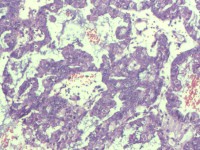

性别

女

年龄

55岁

临床诊断

异常子宫出血

一般病史

阴道不规则出血1月

标本名称

子宫内膜

大体所见

灰白色组织1堆、4*3.4*2.2CM大。

能诊断癌吗

图3

子宫内膜样腺癌

雾蒙蒙:

支持。